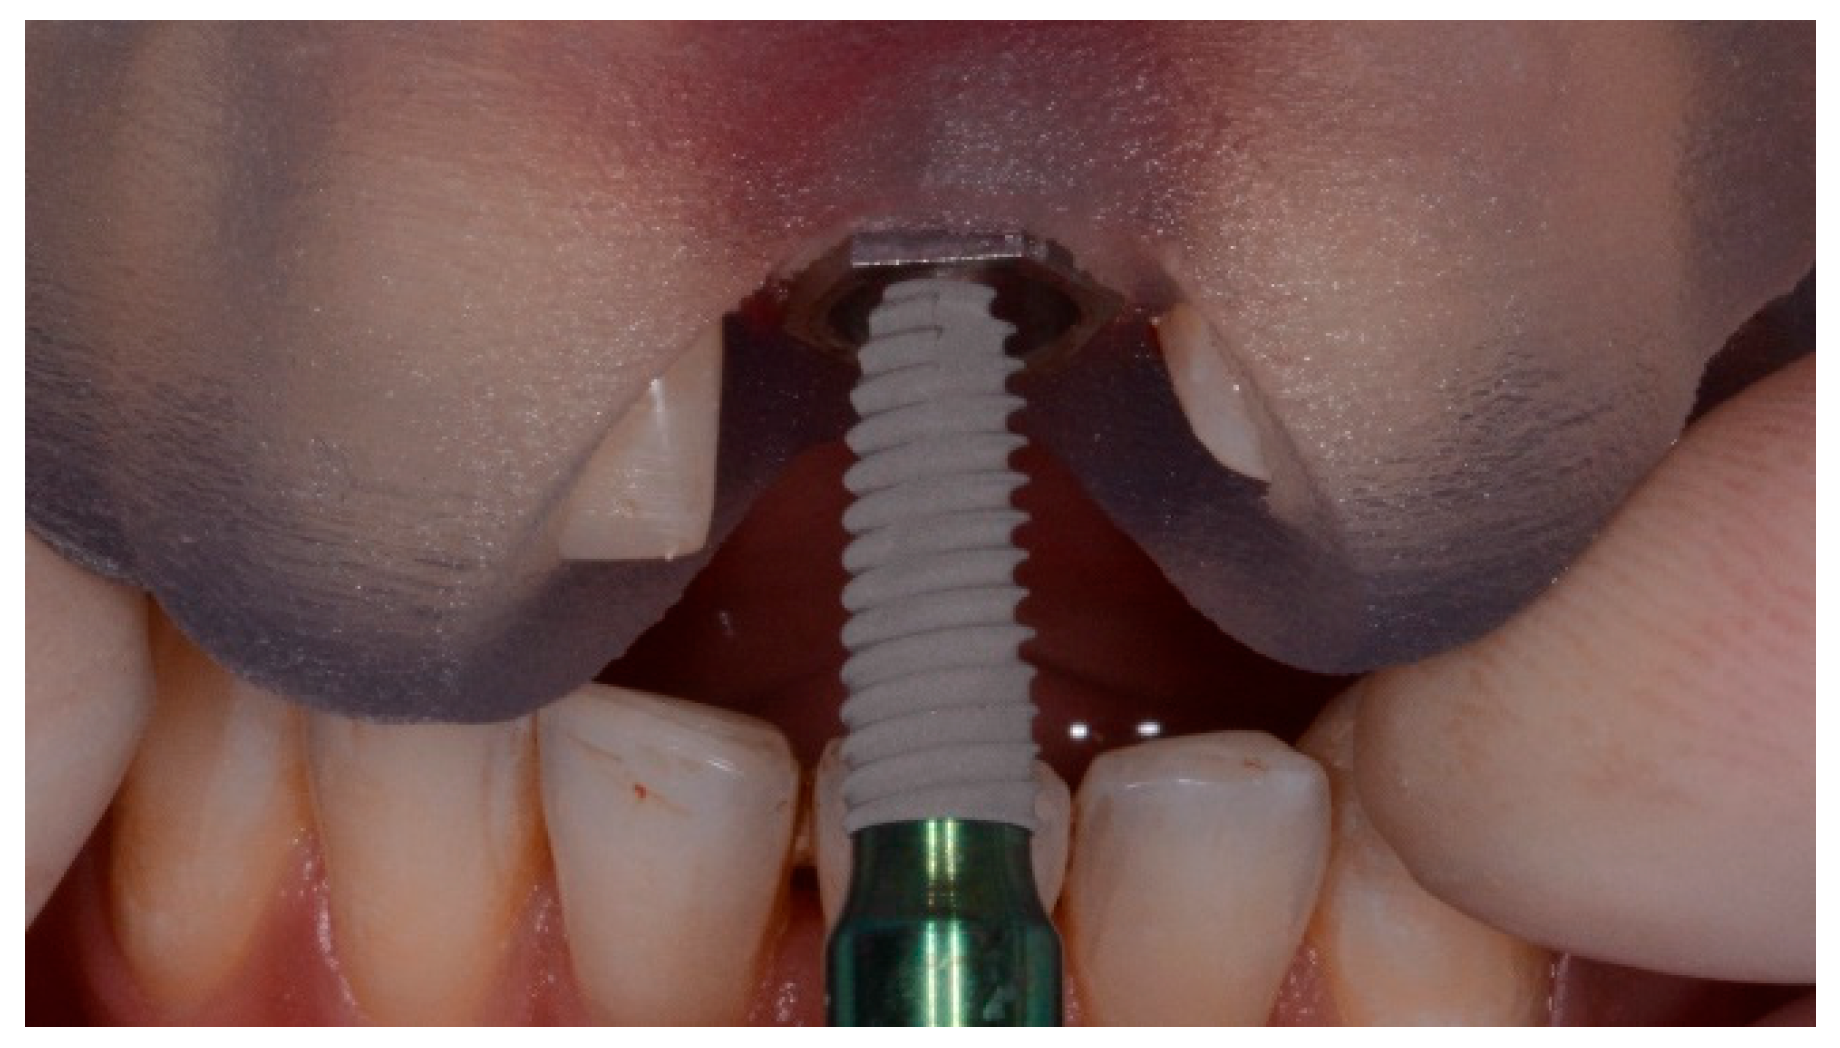

Enrolled patients received preoperative photographs, periapical radiographs or panoramic x-rays for initial screening and evaluation. The prosthetic-driven planning workflow started by taking a cone beam computed tomography (CBCT) scan (Cranex 3Dx, Soredex, Tuusula, Finland) by using a wax bite to separate dental arches. Then, the patients received intraoral digital impression taken using the 3M True Definition Scanner (3M Italia, Pioltello, Milano). The digital data (STL, Surface Tessellation Language) were imported in a 3D design software (exocad DentalCAD, Exocad GmbH, Darmstadt, Germany) to realize a virtual wax-up according to the functional and esthetic requirements. Then, the STL and DICOM (Digital Imaging and COmmunications in Medicine) data were imported in a 3D software planning program (3Diagnosys ver. 5.0, 3DIEMME srl, Cantù, Italy). Then, the reprocessed surface extrapolated from the DICOM data (by using a Hounsfield scale filter) and the surface generated by the master cast scanning process, or by the intraoral scanning process, were merged with the best-fitting repositioning tools of the software (3Diagnosys ver. 5.0, 3DIEMME srl). Afterwards, prosthetic-driven implants/abutments size and location were planned to take into account the bone quality and quantity, soft tissue thickness, anatomical landmarks, as well as type, volume, and shape of the final restoration. After careful functional and esthetic evaluation and final verification, the prosthetic-driven plan was approved. At this point, patients were randomly assigned to receive conventional stereolithographic surgical template with (control group, Figure 1) or without (test group, Figure 2 and Figure 3) metallic sleeves. Stereolithographic surgical templates were designed and fabricated by an independent certified center not previously involved in the study (New Ancorvis srl, Bargellino, Italy). In the test group, conventional templates with close-sleeve-design were produced to place implants between premolars. In case of implants to be placed in molar area, template with open sites were produced to solve interarch space limits.

Figure 1.

Surgical templates with metallic sleeves.